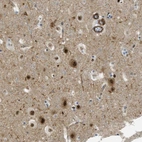

Immunohistochemical staining of human cerebral cortex shows strong nuclear positivity in neurons.